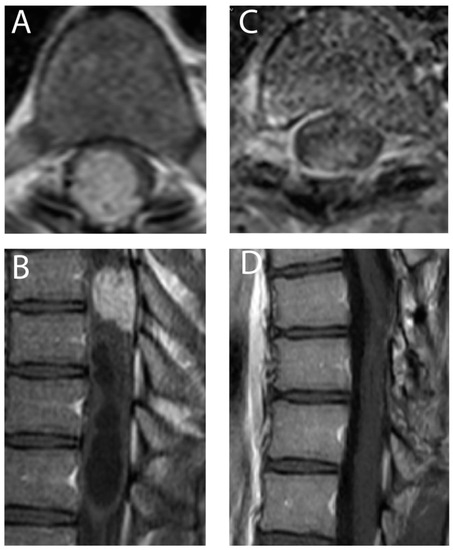

2.2. Surgical Intervention

3.2. Surgical Intervention

| Syringomyelia (N/%) | 20 (74.07%) |

| Von Hippel-Lindau mutation (N/%) | 22 (81.48%) |